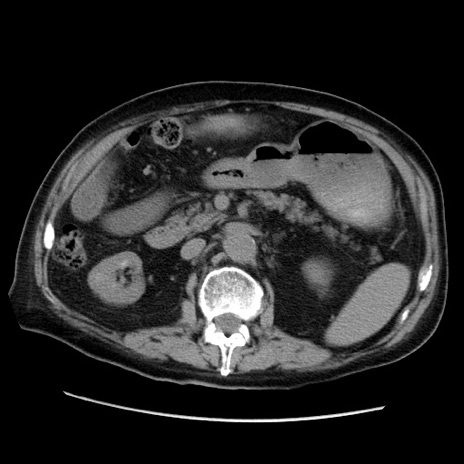

症例21(横断像)

【症例】70歳代男性

【主訴】腹痛

【現病歴】肝硬変・肝細胞癌にてかかりつけの方。約9時間前に食後より腹痛出現。症状が徐々に増悪し、嘔吐出現したため来院。

【既往歴】肝硬変、肝細胞癌(RFA、TACE後)

【身体所見】意識清明、表情苦悶様、BT 36℃、BP 129/78mmHg、P 88bpm、SpO2 97%(RA)、右上腹部から心窩部にかけて圧痛あり、反跳痛なし、筋性防御あり。

【データ】WBC 5800、CRP 0.16